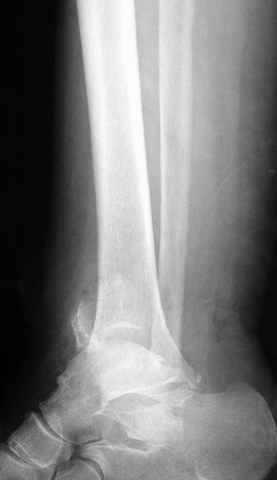

Pilon fracture:

ET> ЕЧ При подобных переломах фиксация малоберцовой кости обеспечивает

ET> низведение латерального тибиального фрагмента - появляется ориентир для

-Появляется ориентир и остов, на чем можно строить восстановление, почему сперва малоберцовую, впервые обьяснили и описали (Pylon type and Ankle fractures) в середине 50х Rienau и Gay.

Восстановливая длину и ротацию малоберцовой кости, затем относительно легче произвести реставрацию остальных элементов перелома дистального эпиметафиза болшеберцовой кости.

где исследования на трупах показали, что малоберцовая кость участвует в стабильности голеностопного сустава, поддерживая наклон тарана (talar tilt) за счет связок. После ознакомления работой Ramsey в ортопедию ввели термин "при переломах голеностопного сустава смещенная

таранная кость следует за малоберцовой костью" т.е. связка не рвется, а тянет таран за собой, поэтому восстановление малоберцовой кости в

первую очередь, затем остальных элементов - стал классическим при лечении данной патолгии. Латеральная колонна (столб), дистальный

конец малоберцевой кости, к нему прикрепляется латеральный суставной фрагмент дистального эпиметафиза большеберцовой кости (как на снимке)

и таранная кость, которые при репозиции малоберцовой кости репонируются автоматически.

Из работ Ramsey and Hamilton, Yablon et., укорочения на 1мм

малоберцовой кости, уменьшает на 42% контактную поверхность между

малоберцевой и таранной кости, которое в свою очередь приводит к

увеличению давления на остальные части суставной поверхности, что

является предпосылкой раннего артроза.